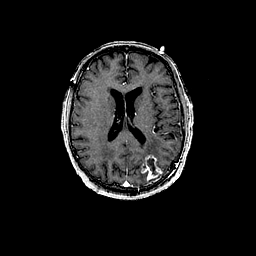

Glioma overlay -- Slice #69

[Home][Help][Clinical] Slice 69